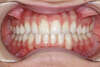

Canine incluse traitée avec des gouttières

Fin de traitement